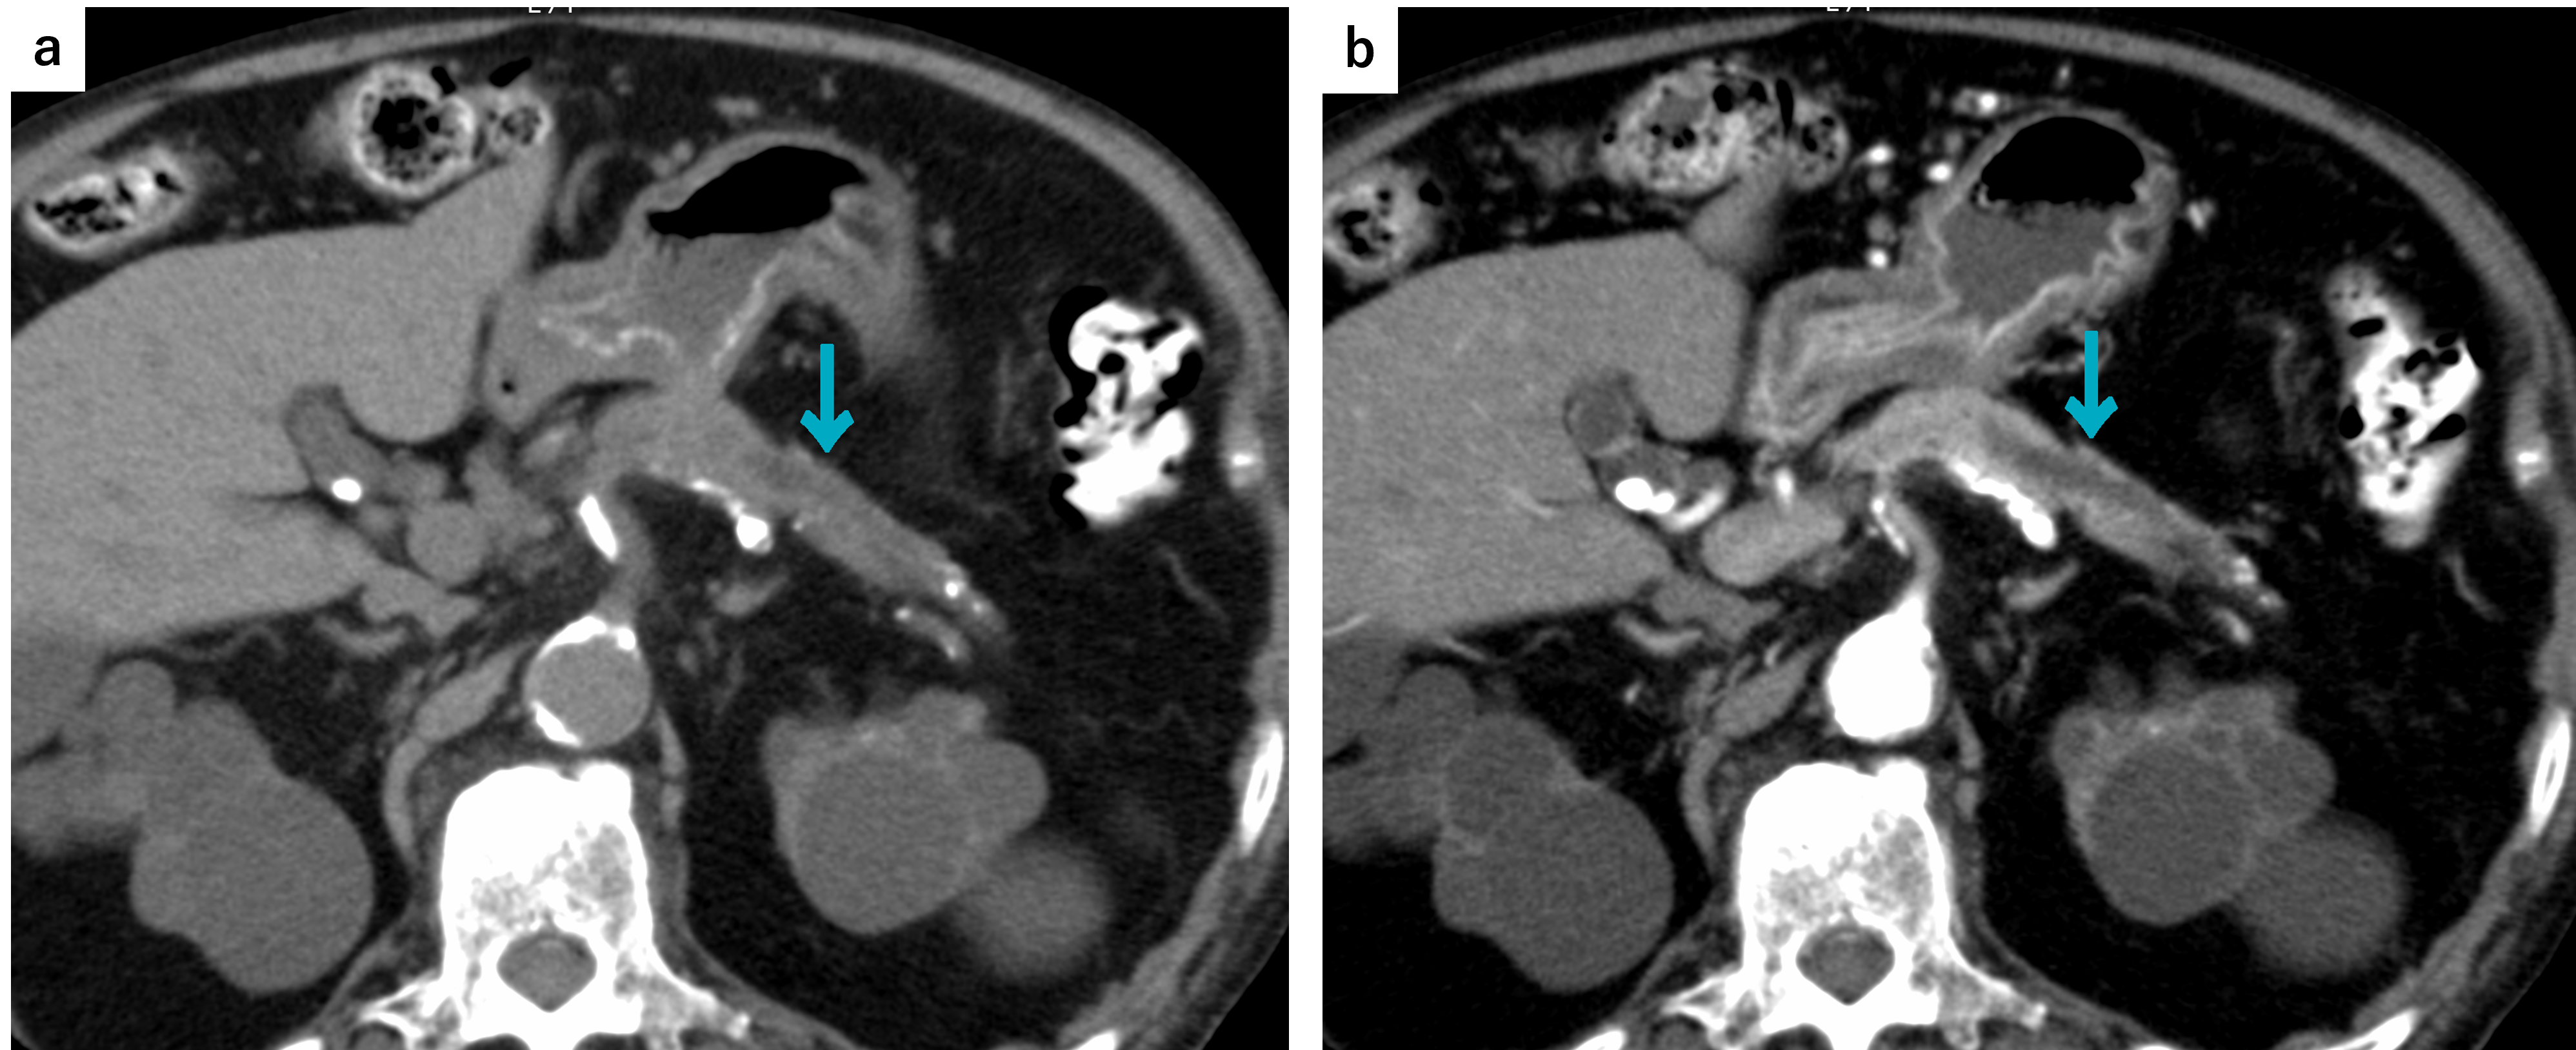

a:単純。単純でも主膵管拡張を認めます。b:膵実質相。膵尾部に急激に拡張する主膵管拡張を認めます。口径差のある部分に腫瘍がある可能性を示唆する所見です。

a:単純。わかりにくいですが,単純でも主膵管拡張を疑う管状構造が確認できます。b:門脈相。膵尾部に管状の低濃度域があり,主膵管拡張の所見です。この症例は膵頭部癌であり,主膵管の拡張を生じています。